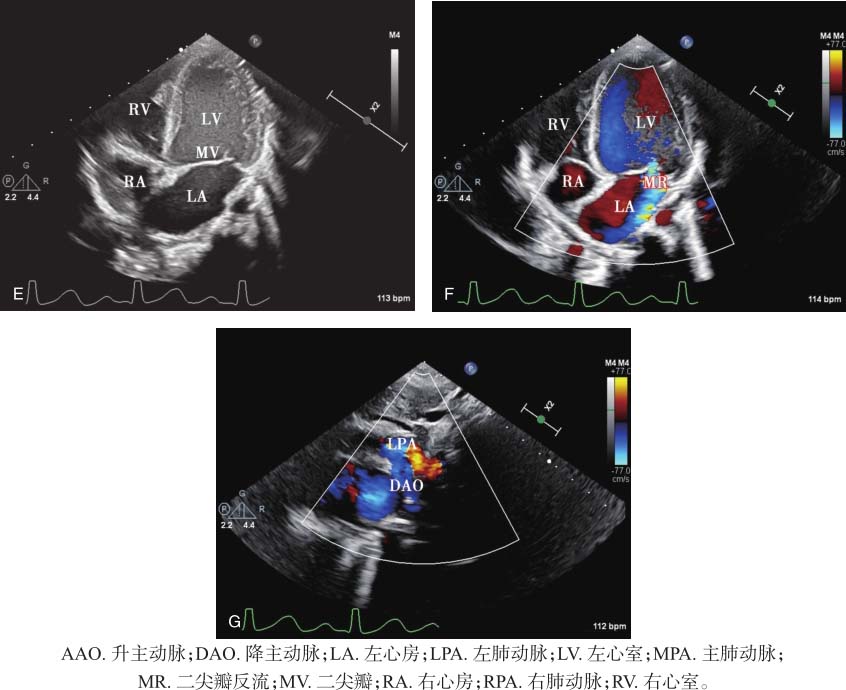

图15-1 患儿超声心动图表现

A.胸骨旁左心室长轴切面显示左心房、左心室内径增大,右心室内径正常;B.胸骨旁肺动脉长轴切面显示降主动脉与左肺动脉开口之间未闭的动脉导管,为管型,降主动脉侧和肺动脉侧内径相近;C.胸骨旁肺动脉长轴切面彩色多普勒显示降主动脉与左肺动脉之间左向右连续性分流信号;D.连续多普勒测量降主动脉与左肺动脉之间分流峰值流速为396cm/s,峰值压差为63mmHg;E.心尖四腔心切面显示二尖瓣环扩大,瓣叶对合缘减小;F.彩色多普勒显示二尖瓣中量反流;G.胸骨上窝切面彩色多普勒显示降主动脉与左肺动脉之间左向右连续性分流信号。

二维超声显示降主动脉峡部和左肺动脉之间导管回声,呈管样,主动脉侧与肺动脉侧内径相近。左心房、左心室内径增大,符合动脉导管未闭导致的左心前负荷增加的血流动力学改变。动脉水平为左向右高速连续性分流,连续多普勒测量分流峰值流速为396cm/s,峰值压差为63mmHg,据此计算肺动脉收缩压不高,患儿尚未出现肺动脉高压。由于左心内径增大,二尖瓣环扩大,导致二尖瓣叶对合缘减小,瓣叶对合不良,二尖瓣中量反流。最终诊断为动脉导管未闭(管型),二尖瓣中量反流。

动脉水平探及左向右连续性分流信号,峰值流速396cm/s,峰值压差63mmHg。二尖瓣中量反流,缩流颈宽约3.7mm。见图15-1。